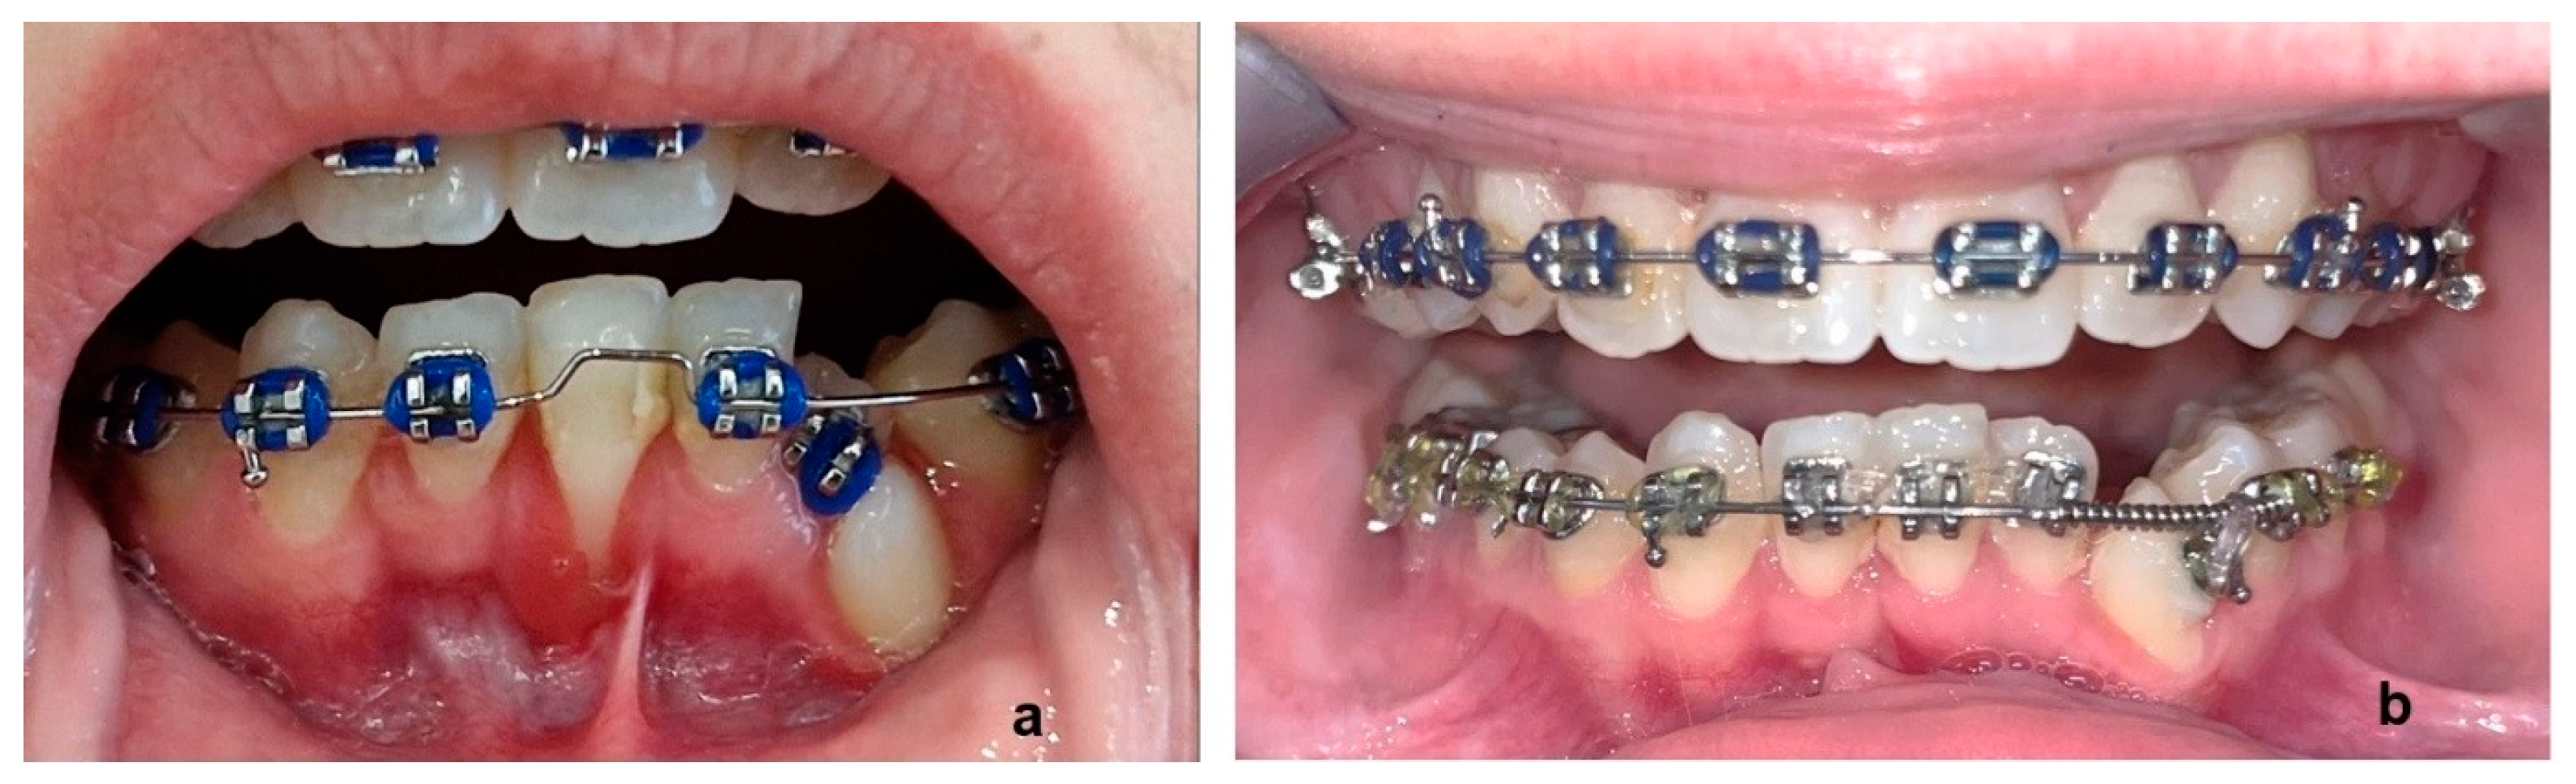

After 43, 42, 32 were brought into the lower arch, it was decided to extract 81, which presented a significant recession (Figure 8a) of the labial gum due to inclination and the general surcharge that it was subjected during mechanotherapy. In this way, additional space was gained for 32 and 33 (Figure 8b).

At the end of treatment, the impacted teeth were restored to their proper place. As only three incisors were present in the lower jaw, inter-proximal reduction was performed in the upper arch in the anterior region, in order to deal with the increased overjet.

Final panoramic (Figure 9a) and lateral cephalometric X-ray (Figure 9b) and tracing (Figure 9c), as well as before and after treatment tracing superimposition (Figure 9d), are presented in Figure 9. Skeletal Class II relationship was reduced (ANB was calculated 5° at the end of therapy from 8° at the beginning (Table 2)), while Class I molar and canine relationships were achieved (Figure 10 and Figure 11). In Figure 12, a graphical abstract of the timeline of the steps that were followed in the treatment of this DTE case is presented.

Figure 8. Intraoral progress photos before (a) and after extraction of 81 (b).